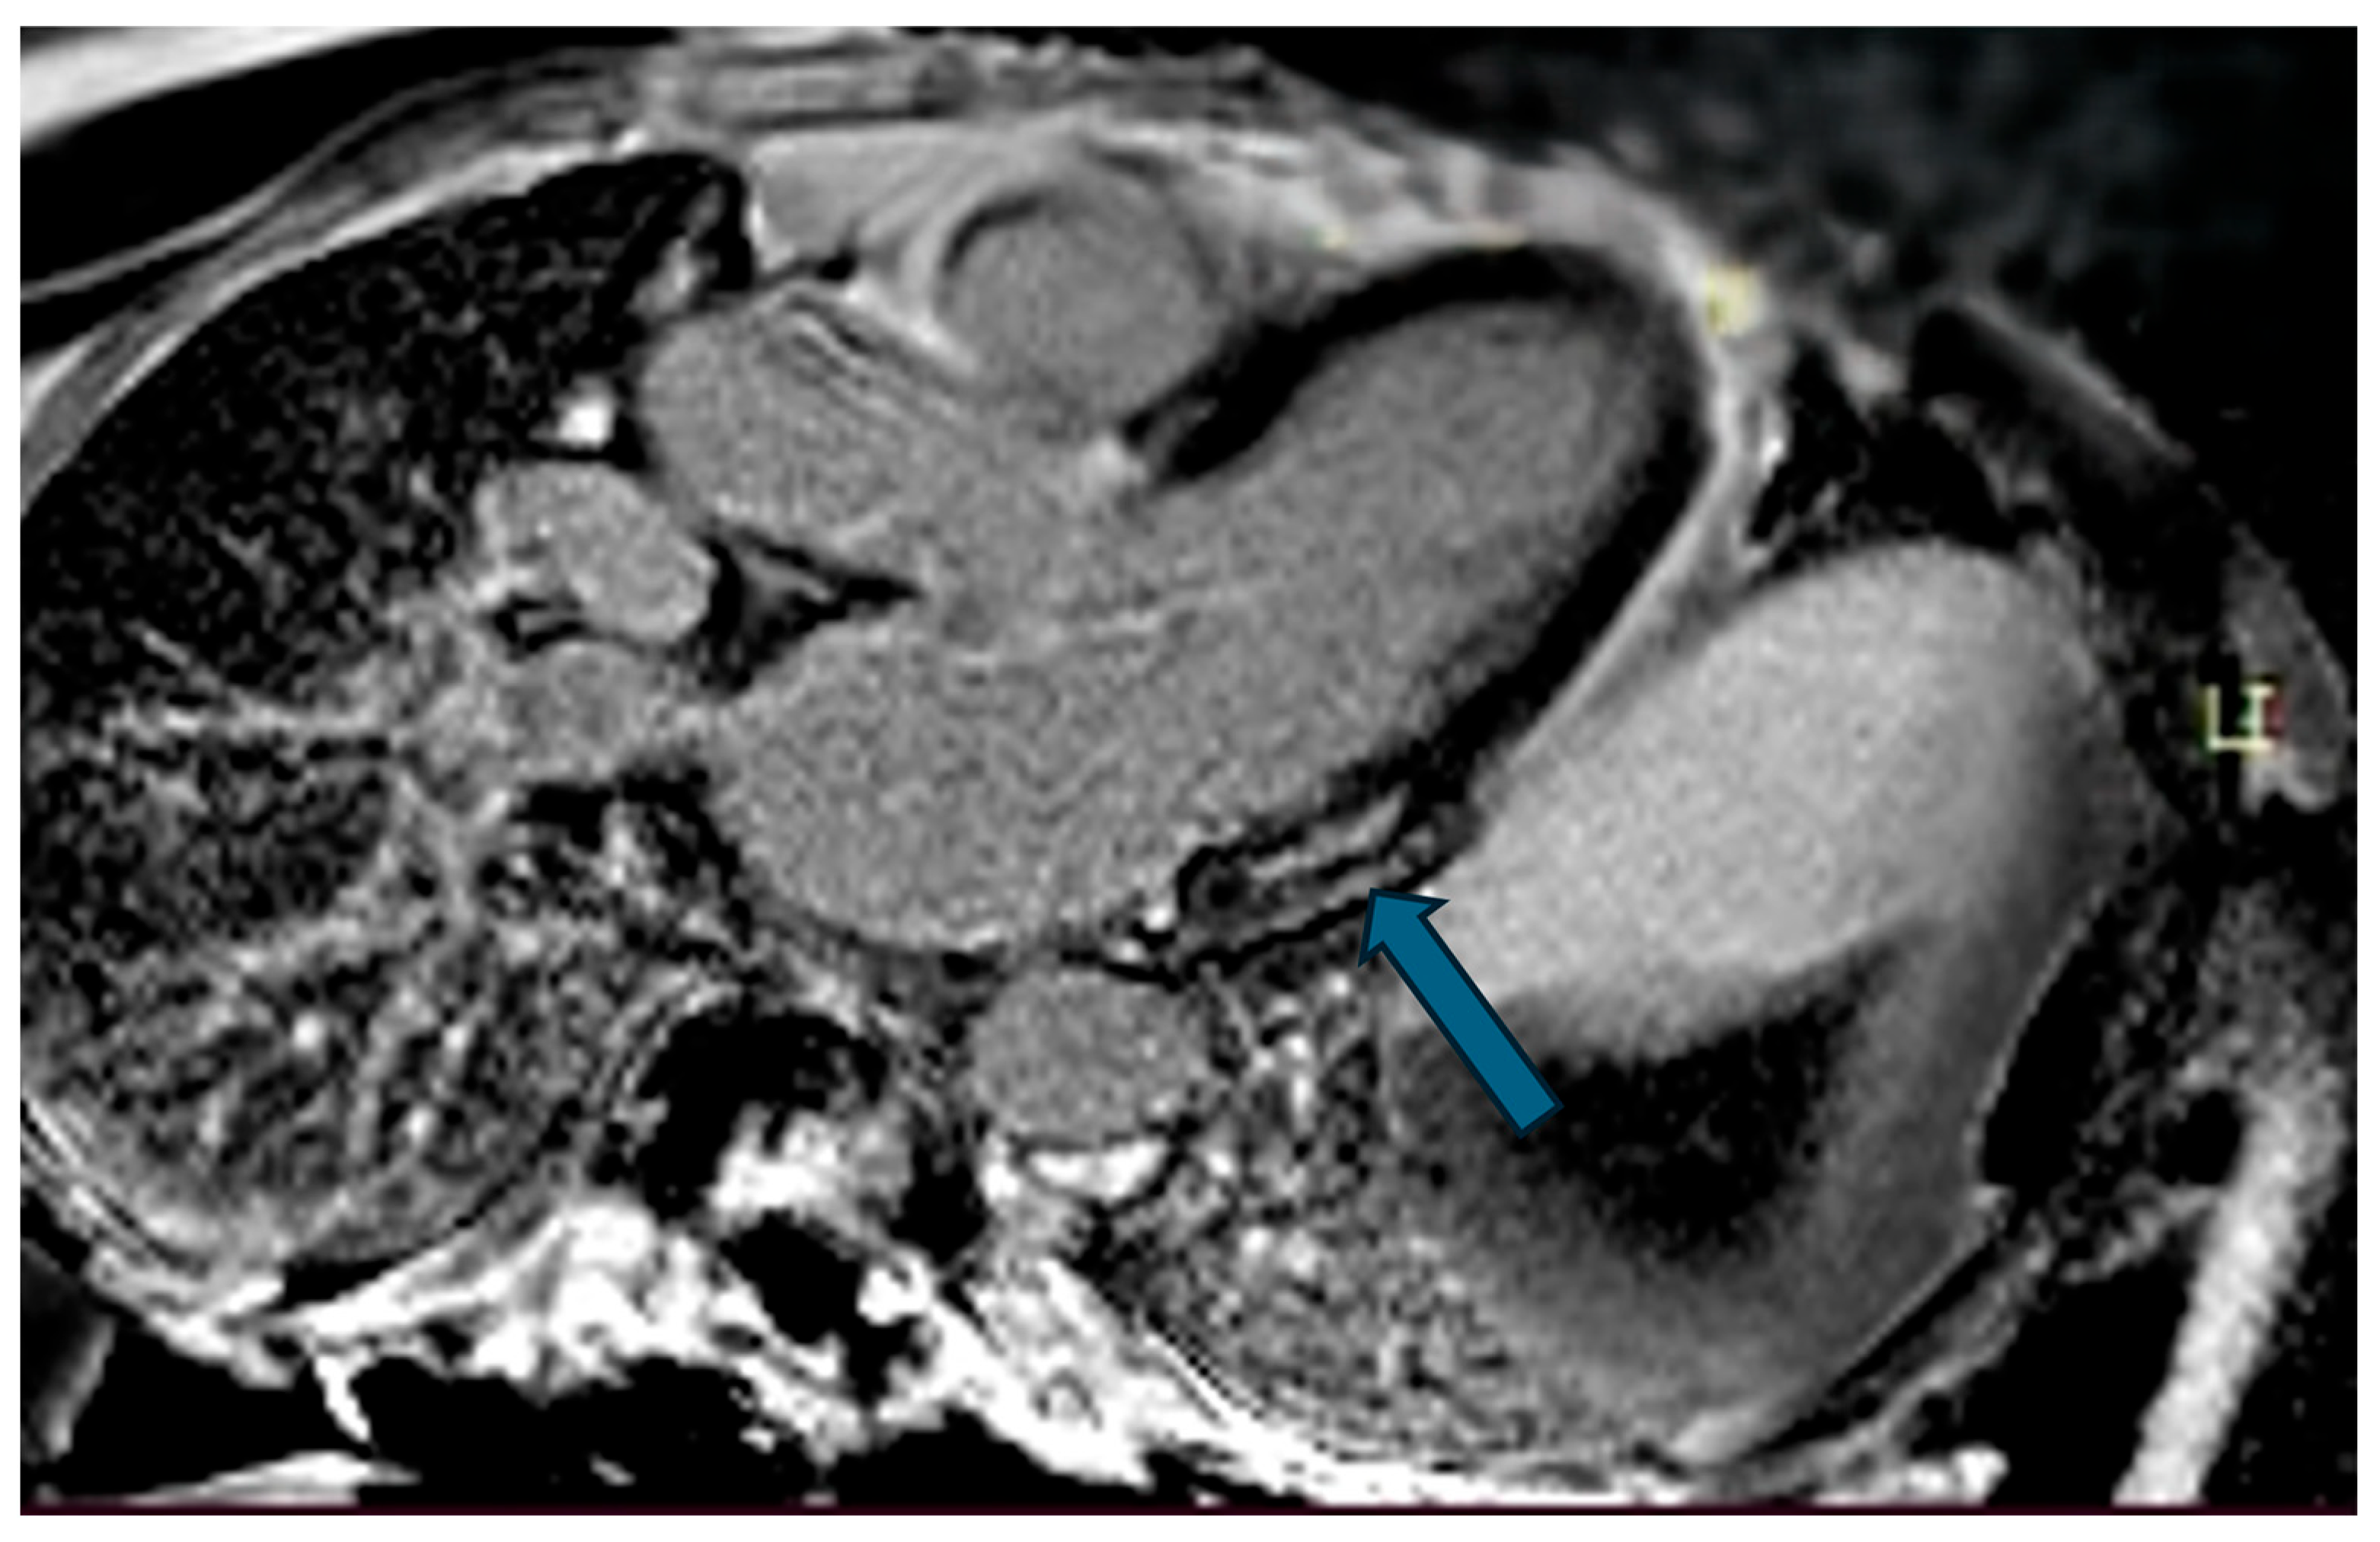

| Case | Patient (Sex, Age) | Symptoms | MAD (mm) | Valvular Issues | LGE | Other Details |

|---|---|---|---|---|---|---|

| 7 | Female, 53 years old | Extrasystole and syncope | 15 | MVP, valvular regurgitation | Basal-lateral | Extensive MAD with MVP and LGE; increased arrhythmic risk; antiarrhythmic therapy considered. |

| 8 | Female, 63 years old | Aortic and mitral regurgitation | 11 | Aortic and mitral regurgitation | Lateral | Aorto-mitral regurgitation with septal hypokinesia; mitral valve repair performed; heart failure therapy started. |

| 9 | Male, 45 years old | Palpitations and vertigo | 10 | - | Lateral | Basal lateral LGE; regular clinical and ECG follow-up recommended |